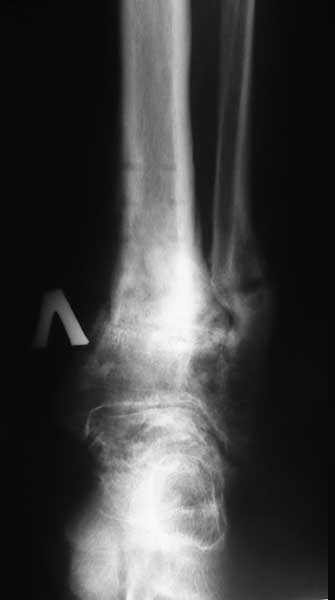

Уважаемые коллеги. Пациентка 1948 г.р., беспокоят боли в области левого голеностопа, прогрессирующая деформация(варусная) и неустойчивость сустава.Травму отрицает. Болеет более 5-ти лет. Согласна на операцию. Вопрос об артродезе г/ст сразу не вызывал сомнений. Но, если это артропатия, то насколько велик риск несращения? Помогите определиться с диагнозом и сответственно с тактикой. Невролог патологии не находит. Во вложенных файлах рентгенограммы за 2007 и 2012 гг.? фото и КТ свежая.

Вопрос, как я писал, в том что это такое- артропатия или артроз. Мне, например, не доводилось видеть нетравматический остеоартроз голеностопного сустава с прогрессирющей варусной деформацией и выраженной кистозной перестройкой. А несращение после резекции голеностопа у больного артропатией видел. В том случае коллеги дважды фиксировали блокирующим гвоздем и пациент ходил, пока держал металл и в настоящий момент планируется 3 синтез.

У пациентки резко выраженная вальгусная деформация стопы. При попытке выполнения артродеза без коррекции оси конечности вероятность несостоятельности артродеза и сохранения болей крайне велика. Артроз имеет односторонний характер и связан, с большой степенью вероятности, с нарушением оси конечности. При восстановлении правильной оси такой сустав сможет послужить еще не один год. В плане дообследования обязательны снимки в переднезадней проекции под нагрузкой с захватом бугра пяточной кости, которые помогут лучше оценить осевые взаимоотношения голени и стопы. Исправить эти взаимоотношения можно, как путем медиализирующей остеотомии пяточной кости, так и путем остеотомии большеберцовой кости. Сохраняющая голеностопный сустав хирургия сейчас на подъеме, ей посвящаются симпозиумы, статьи. Она служит, как для сохранения сустава, так и для подготовки последующих успешных операций артродезирования или протезирования.

Да, лучше бы сразу фото двух стоп выложили. А то уж больно первая фотография на вальгусную деформацию похожа. И все-таки ось голени и стопы должна быть восстановлена тем или иным способом. Без этого вероятность несостоятельности артродеза очень велика.